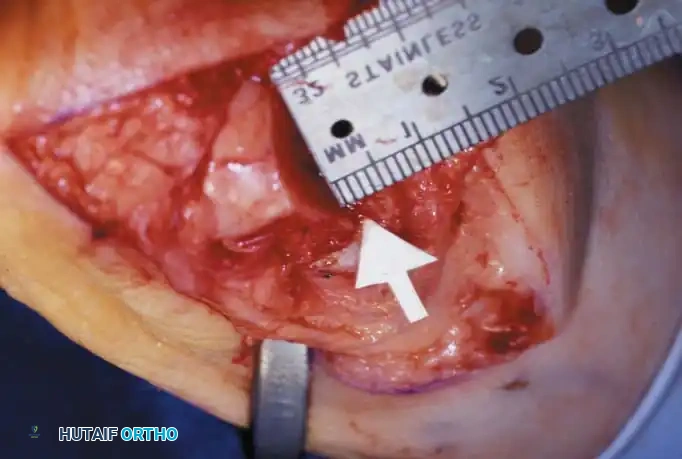

• Using a Freer elevator or a small osteotome for its strength, mobilize the fi bular sesamoid (Fig. 78-31A to C). This may be diffi cult in elderly patients with signifi cant deformity and adherence of the sesamoid to the metatarsal head. Lift the metatarsal dorsally for exposure (Fig. 78-31D and E).

Fig. 78-31 Excision of fi bular sesamoid in modifi ed Keller procedure. With base of proximal phalanx removed and medial eminence excision, exposure of fi bular sesamoid is not as diffi cult from medial incision. A, Operative photograph showing elevation of fi rst metatarsal with strong two-tooth retractor and use of small osteotome to mobilize fi bular sesamoid and lateral capsuloligamentous (frequently contracted) structures. Osteotome is between metatarsal head and lateral sesamoid. When mobilization of fi bular sesamoid is complete, entire sesamoid is visible for excision. Note chondromalacia of tibial sesamoid articular surface medial to osteotome. B, Fibular sesamoid has been excised, and lateral capsular structures and conjoined tendon (in forceps) have been released. Neurovascular bundle to lateral side of hallux is adjacent to these structures. C, Diagrammatic representation of modifi ed Keller procedure. By excising fi bular sesamoid, valgus moment of conjoined tendon of fl exor hallucis brevis and adductor hallucis no longer pulls fl exor hallucis longus tendon laterally (carrying hallux with it) through capsulosesamoid plantar plate and pulley system. D, Metatarsal head must be lifted dorsally to excise fi bular sesamoid under direct vision. E, Note exposure of fi bular sesamoid after mobilization of metatarsal head. Continued